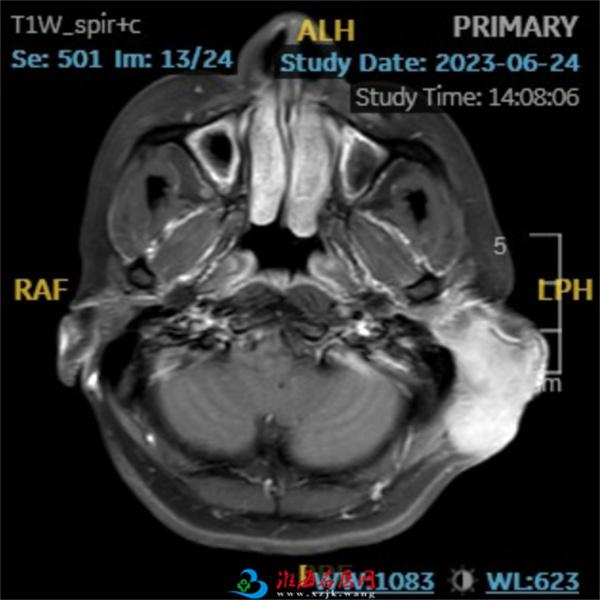

术前CT、MR检查

今年32岁的李女士,半年前发现左耳后肿物,无疼痛,曾在外院进行手术治疗,术后病理回示:恶性周围神经鞘膜瘤。然而2月前发现左耳后肿物复发,病灶持续性增大,约鸭蛋大小,表面红肿,皮温不高,无明显疼痛,活动度差,无明显破溃、流脓,为求进一步治疗,患者到我院耳鼻喉科就诊。

患者左侧耳后肿物,皮肤呈暗紫色,术后瘢痕样增生,质韧,活动度欠佳,约10*11cm大小